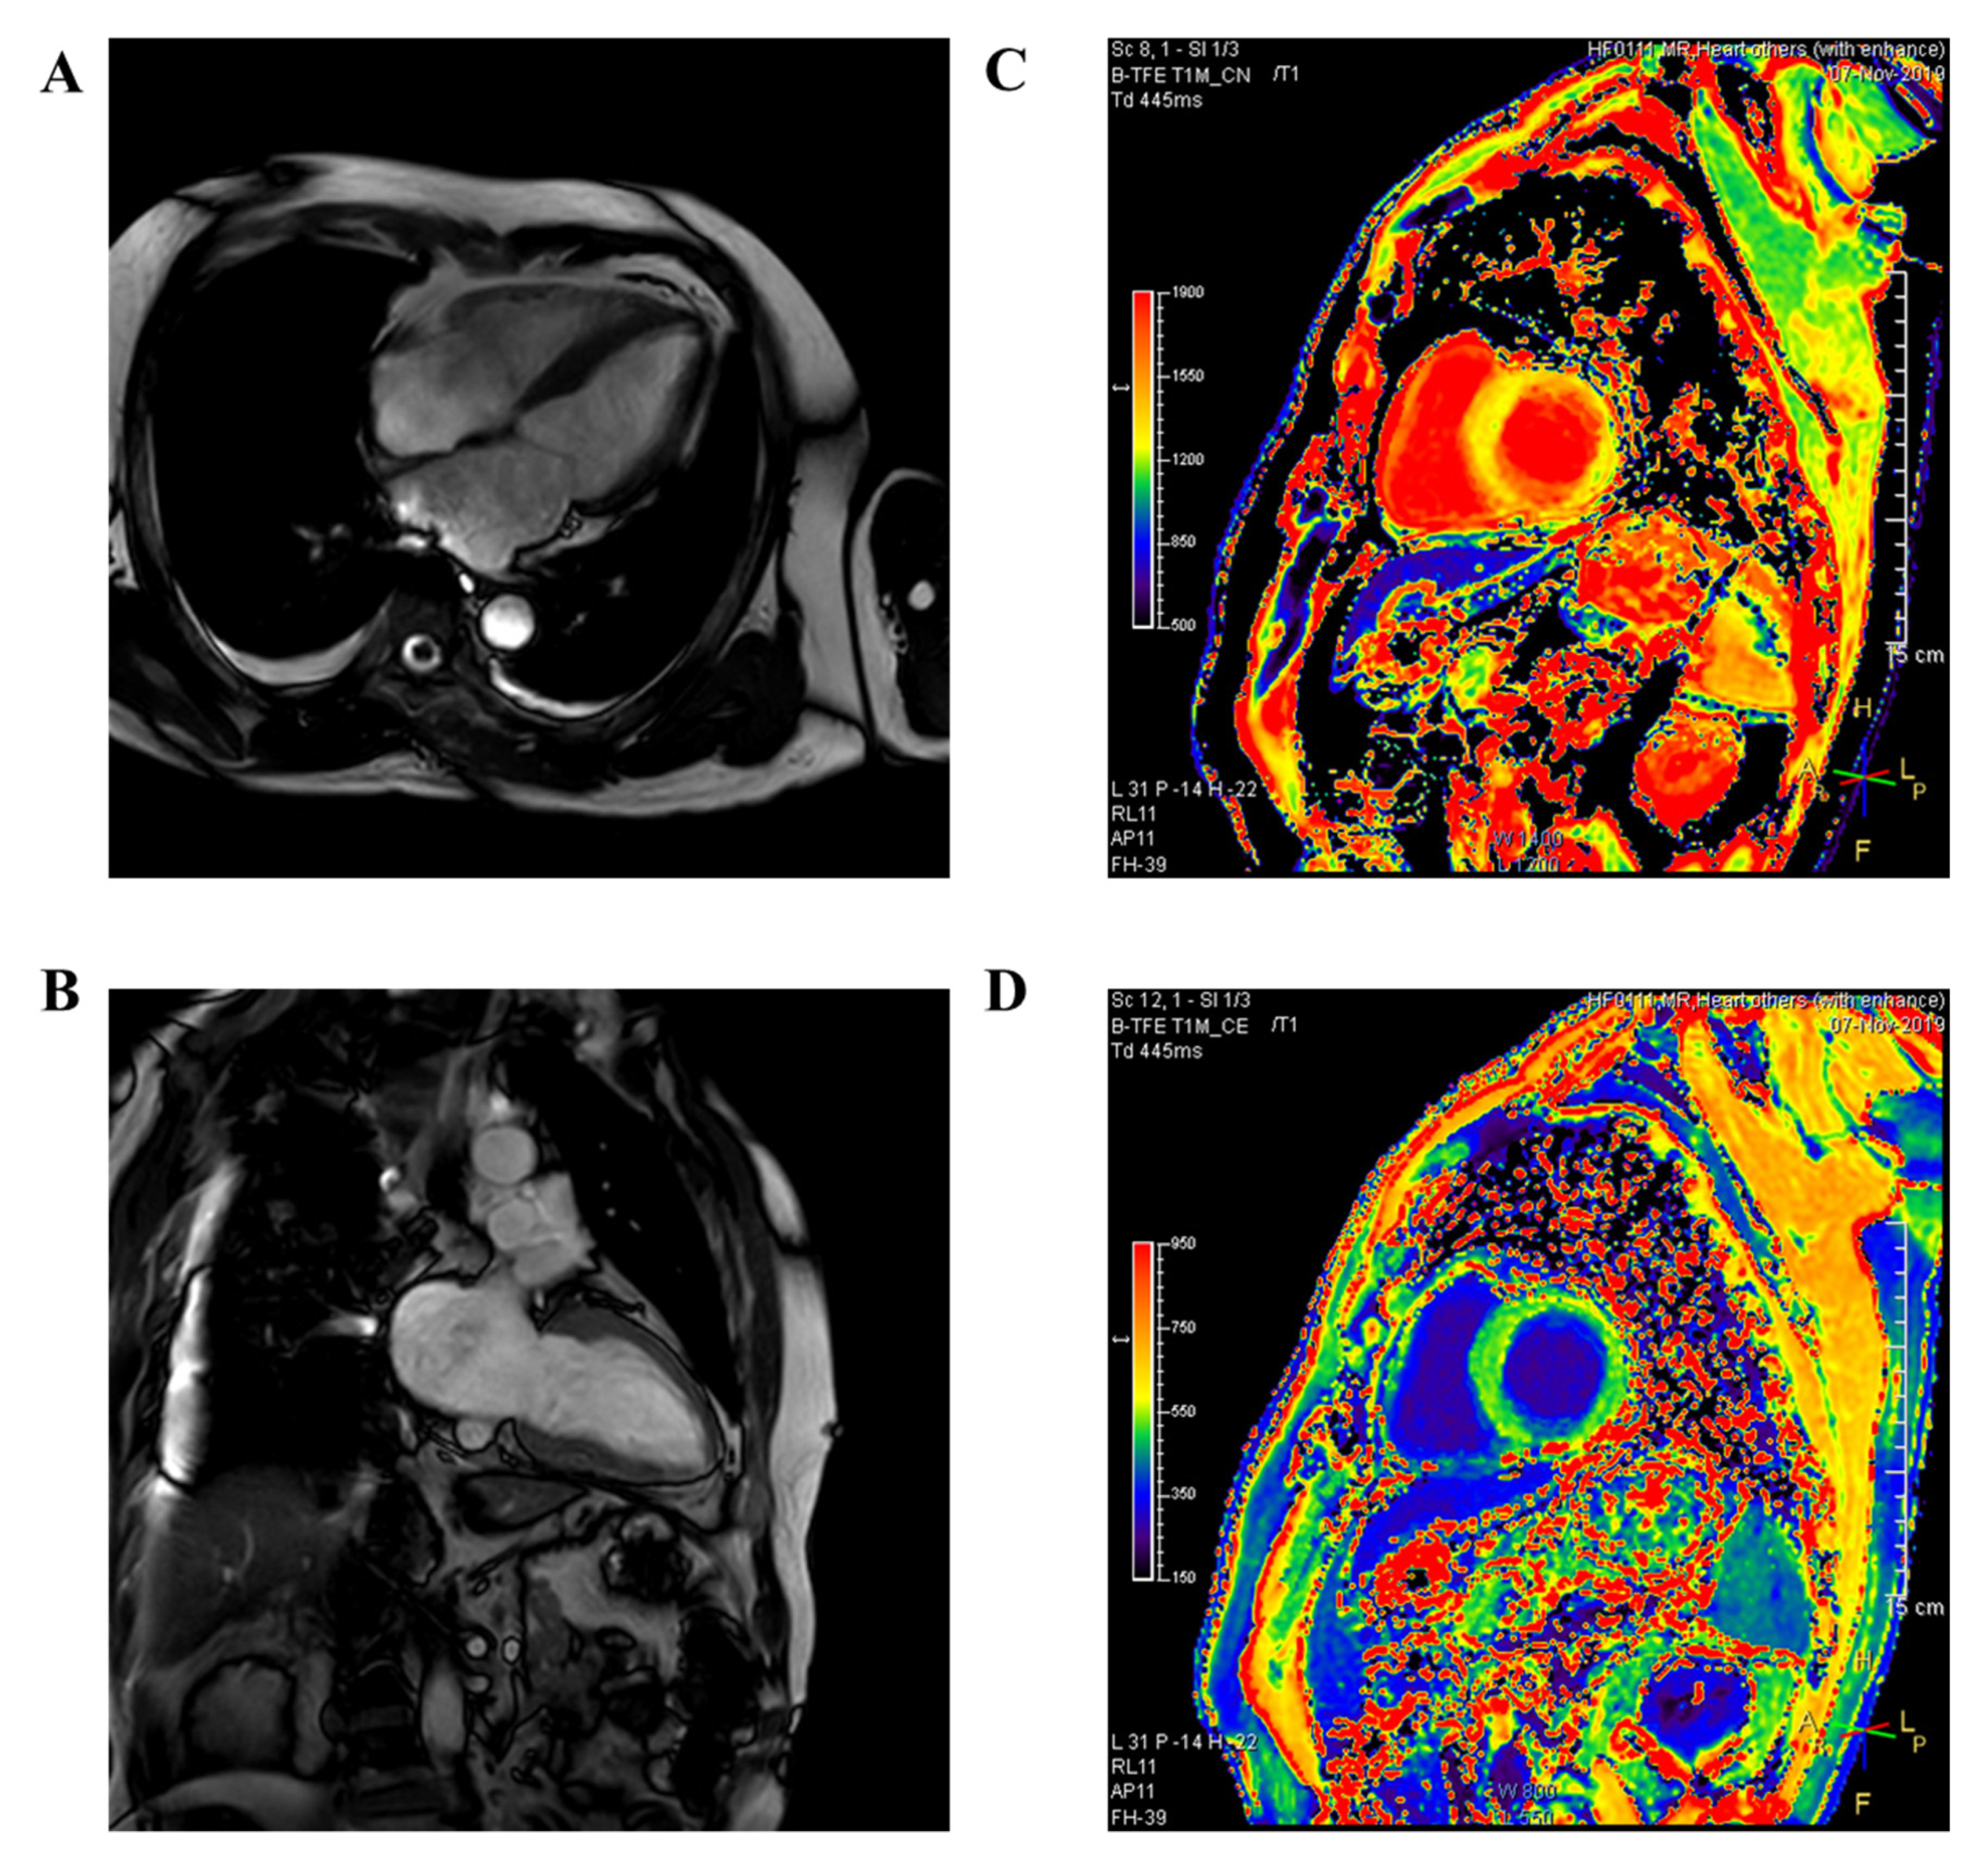

2.4. CMR Imaging Acquisition and Analysis